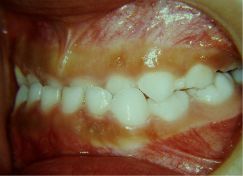

Soggetto asiatico con morso inverso anteriore completo.

Crescita scheletrica tendente alla terza. Impossibilita di determinare il carico genetico del problema.

finalmente la paziente comincia il trattamento intercettivocon il damon 4 x 2

inserimento e funzionalizzazione di 4x 2

le molle open coil agiscono sviluppando il mascellare superiore e correggendo il rapporto di classe dentale ,lentamente e dolcemente ,le forze leggere continue possono correggere il problema iniziale che altrimenti avrebbe preso il sopravento nella crescita della bimba .

corretto il crossbite si partecipa alla corezione dentale lentamente e dolcemente.